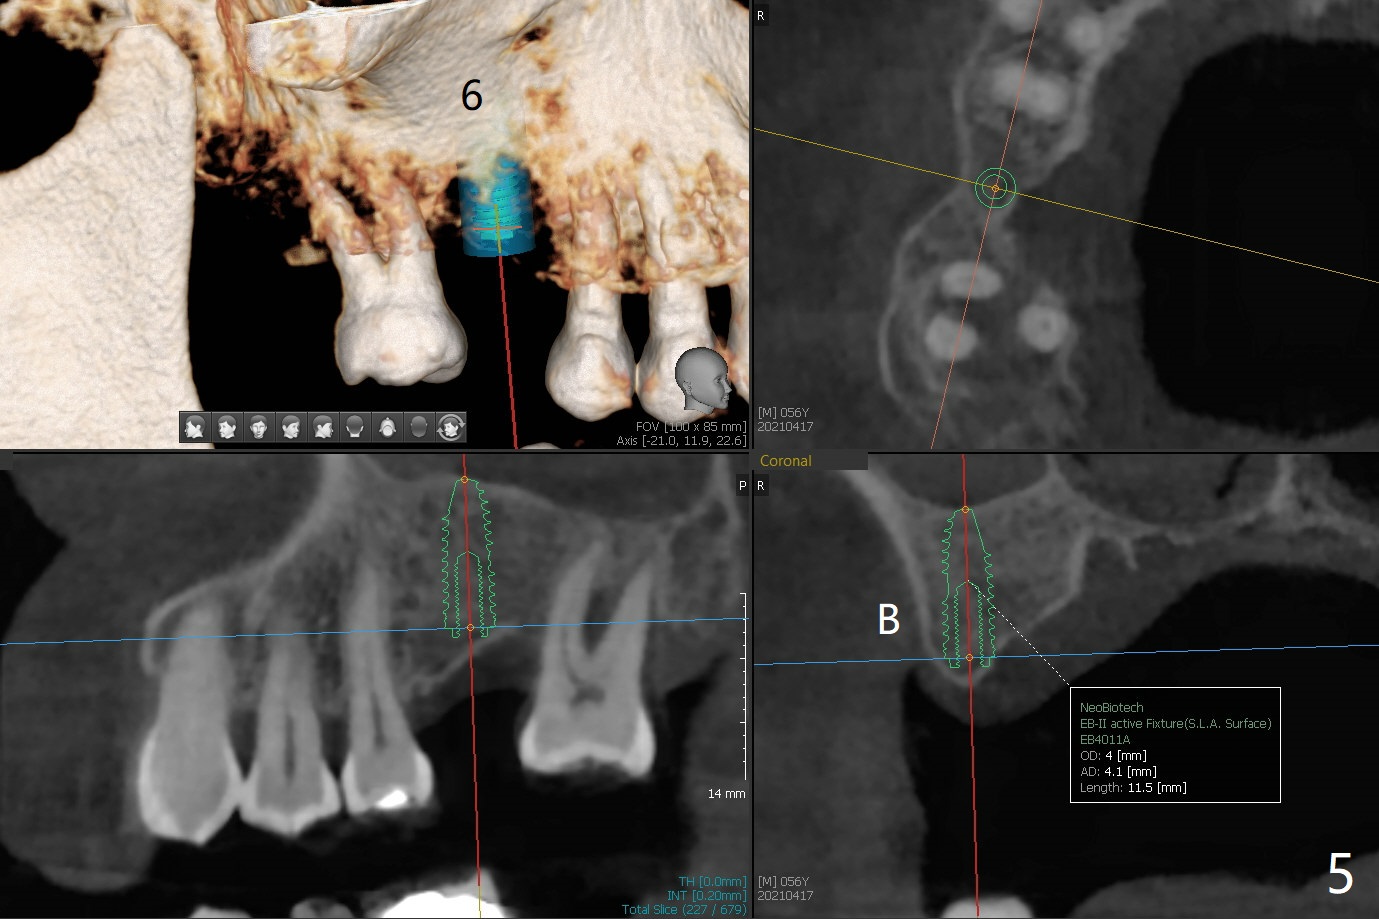

56岁男右下7位点保存一个月,还缺失4个牙齿(图一),左下2,3牙槽嵴特别狭窄,骨皮质为主(图二),应该植入2.0,2.5毫米植体(图三,四),避免复杂植骨术。而右上3骨质也狭窄,但是骨质密度低,几乎松质骨(图五),如果采纳骨膨胀术(高速倒转),植体可以大于4.0毫米,防止植体断裂。左上7骨质宽,但是短,5x8.5毫米植体可能胜任功能(图六)。如果植入10毫米植体,需要做上颌窦提升。